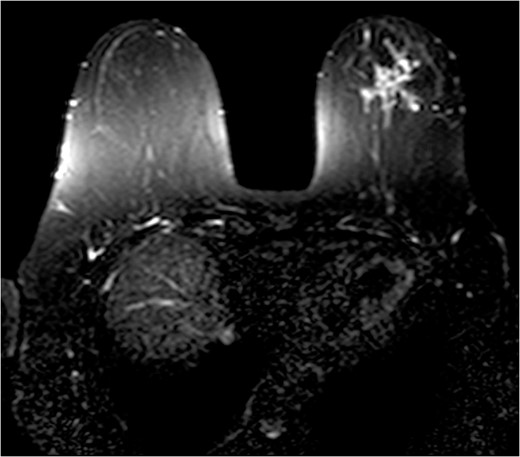

The patient was then sent for MRI of the breast to detail the extent of the remaining mass. This revealed an ill-defined mixed linear and fine nodular enhancing tumor 6.5 × 4.6 × 4.8 cm in size with BI-RADS 5 (Figs 4–7).

Due to the location of the residual lesion posterior to the nipple and its large size, simple mastectomy with sentinel lymph node biopsy was performed with immediate breast reconstruction. Breast conservation surgery was not considered secondary to the location and size. Histology showed a focus of ductal carcinoma in-situ (DCIS) with micropapillary growth and a secondary synchronous invasive ductal carcinoma 0.7 × 0.4 × 0.3 cm adjacent to the lesion. Four lymph nodes were excised and all negative for invasive characteristics. Staging indicates a T1N0M0, Stage I lesion.

The role of MRI in identifying the extent of breast carcinoma is widely reviewed. EPC has been noted to have multifocal hyperintensities at T1 weighted imaging. Contrast MRI will reveal enhancement of the cystic wall, septa and mural nodules [4].